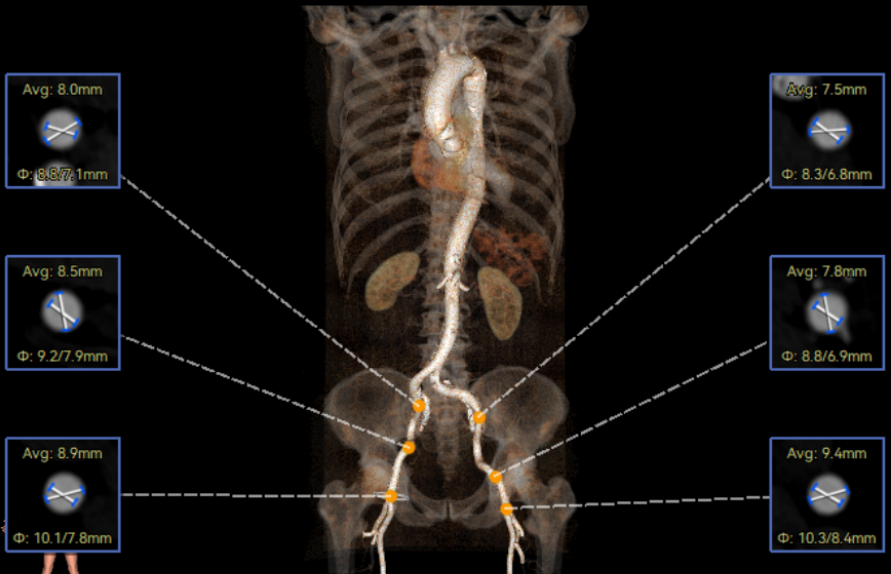

李有金教授 宁夏回族自治区人民医院 “随着人口老龄化加剧,主动脉瓣狭窄患者数量逐年增多,其中高龄、合并多种基础疾病的复杂病例占比不断提升。经导管主动脉瓣置换术(TAVR)作为微创治疗技术,已成为此类患者的重要治疗选择。对于高龄、有恶性肿瘤病史的患者而言,手术的安全性、微创性与长期疗效同等重要,既要最大程度降低手术创伤与并发症风险,也要确保瓣膜的耐用性与患者术后生活质量。 全球首款预装干瓣ProStyle A®的临床应用,为复杂病例治疗提供了全新解决方案。该瓣膜无需术中戊二醛冲洗,大幅缩短了手术操作时间,尤其适合高龄、心功能欠佳的患者。其独特的抗钙化工艺与优化的瓣架设计,既保证了瓣膜的长期耐久性,又能有效规避冠脉风险,为患者的“全生命周期管理”奠定了坚实基础。” 病例简介 现病史:患者半月余前突发抬头时一过性头晕,持续数秒钟,每日发作3-5 次,伴天旋地转感,症状可自行缓解。2025年12月12日就诊于外医院,心脏彩超提示“主动脉瓣狭窄(重度)并关闭不全(轻度),左室壁增厚,升主动脉增宽,左心室收缩功能正常,舒张功能减退”,建议转上级医院诊治。为求进一步治疗,患者就诊我院,门诊以“主动脉瓣狭窄”收住入院。 既往史:胃癌,胃大部切除术后五年。 临床诊断:“1.主动脉瓣狭窄伴有关闭不全(重度狭窄伴轻度关闭不全);2.主动脉瓣钙化;3.肥厚性非梗阻性心肌病;4.心功能不全;心功能III级(NYHA分级);5.升主动脉扩张;6.胃恶性肿瘤个人史” 术前CT评估显示:Type-1型二叶瓣,R-N钙化粘连,瓣叶重度钙化,主要分布在无冠窦瓣叶游离缘、R-N对合缘粘连处及右冠窦基底部;钙化积分933.2mm³;主动脉瓣环直径26mm,LVOT 27.6mm;双侧瓣叶开口高度可,左冠开口高度22.0mm,右冠开口高度20.0mm;主动脉水平夹角57.7°,左室内径偏小;主动脉弓部75.1°锐角弓;外周入路无明显迂曲及钙化,双侧股动脉内径可,右股中分叉。 手术策略 右侧股动脉为主入路,左侧为辅助入路,20F大鞘,股骨头中段穿刺;预装金仕生物 ProStyle A® AV26瓣膜,备29瓣膜,22mm球囊预扩;初始定位对齐瓣环上5mm超高位释放,释放过程中使瓣膜自然下滑至工作位,最终理想位置零位,利用瓣上锚定与封堵,规避冠脉风险;术前适当补液; 手术过程 Step1:主动脉根部造影; 主动脉根部造影 Step2:使用“先瑞达”22mm球囊预扩,无腰无漏,冠脉充盈良好; 球囊预扩 Step3:将ProStyle A®预装干瓣送至目标位置,初始定位后缓慢释放,观察瓣膜自然下滑至理想工作位; 定位 释放至工作位观察 Step5:瓣膜完全释放后,再次造影,显示瓣膜位置、形态良好,导管测平均跨瓣压差由术前60mmHg-降至1mmHg,冠脉血供正常; 最终造影 Step6:术后即刻超声监测,人工瓣膜位置固定,瓣叶启闭无受限,瓣周少量反流。 术后患者病情稳定,已于一周后出院。 结语 作为宁夏回族自治区心血管疾病诊疗的核心高地与区域医疗中心建设的标杆单位,宁夏回族自治区人民医院始终坚守“敬佑生命、救死扶伤”的医者初心,以“技术引领、学科兴院”为发展理念,在心脏大血管领域持续深耕,构建了集“精准评估-个性化方案-微创治疗-全程康复”于一体的诊疗体系。此次西北首例ProStyle A®预装干瓣植入手术的圆满成功,不仅是医院在复杂结构性心脏病介入治疗领域的又一突破性成果,更彰显了医院在引进前沿技术、转化创新器械、服务复杂重症患者方面的责任与担当。 Prostyle A®预装干瓣——助力临床最优化解决方案: 预装干瓣 便捷顺安:金仕生物专利抗钙化技术运用纳米技术去除组织内的细胞碎片和磷脂,封闭游离醛基,从根本上阻断了瓣膜钙化的多项因素,显著提升了瓣膜的耐久性;同时,相比较传统戊二醛保存方式,干式存储最大限度的保留心包的亲水亲油平衡,还原组织天然曲柔性,进一步保障了瓣叶开合,保证长期耐久性; 平衡径向支撑力:Prostyle A®瓣架网孔比例按照病例解剖结构的特殊设计,使瓣膜在狭窄最重的地方良好的撑开,同时避免对瓣环及周边组织的过度压迫,有效降低传导阻滞风险; 精准释放:底部桶状设计更易迅速锚定,协同释放张力小,助力最终精准释放; 过弓柔顺:较细的输送系统直径+亲水涂层,显著提升输送系统通过性,有效减少血管并发症的发生,内连鞘版本最小尺寸等效14F大鞘; 专家简介 李有金 宁夏回族自治区人民医院(点击查看专家详细简历) · END ·